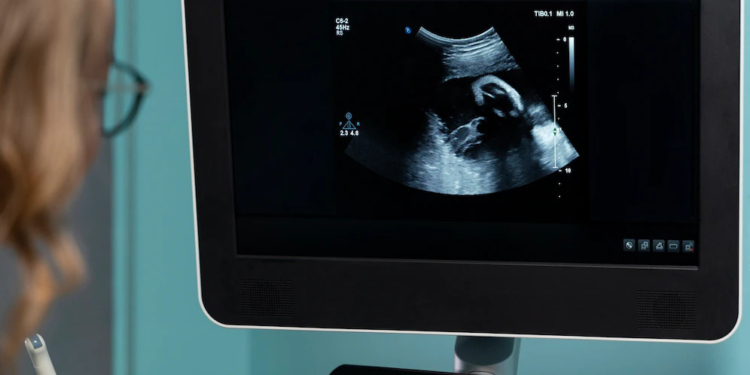

Ультразвуковое исследование (УЗИ) является важной частью определения и лечения бесплодия. Выполняется с помощью специального оборудования и датчика, которым в стандартном случае проводят по животу. Ультразвуковые волны сравнительно безопасны и само исследование безболезненно, поэтому УЗИ используется на различных сроках беременности.

Ультразвуковая диагностика занимает важное место в мониторинге лечения бесплодия. В зависимости от показаний может использоваться на разных этапах терапии и с различной целью. Основные техники проведения УЗИ:

В некоторых случаях во время самой процедуры ЭКО может использоваться ультразвук. Например, во время извлечения яйцеклетки применяют иглу с ультразвуковым наведением. Также начали практиковать перенос эмбрионов под контролем ультразвука.